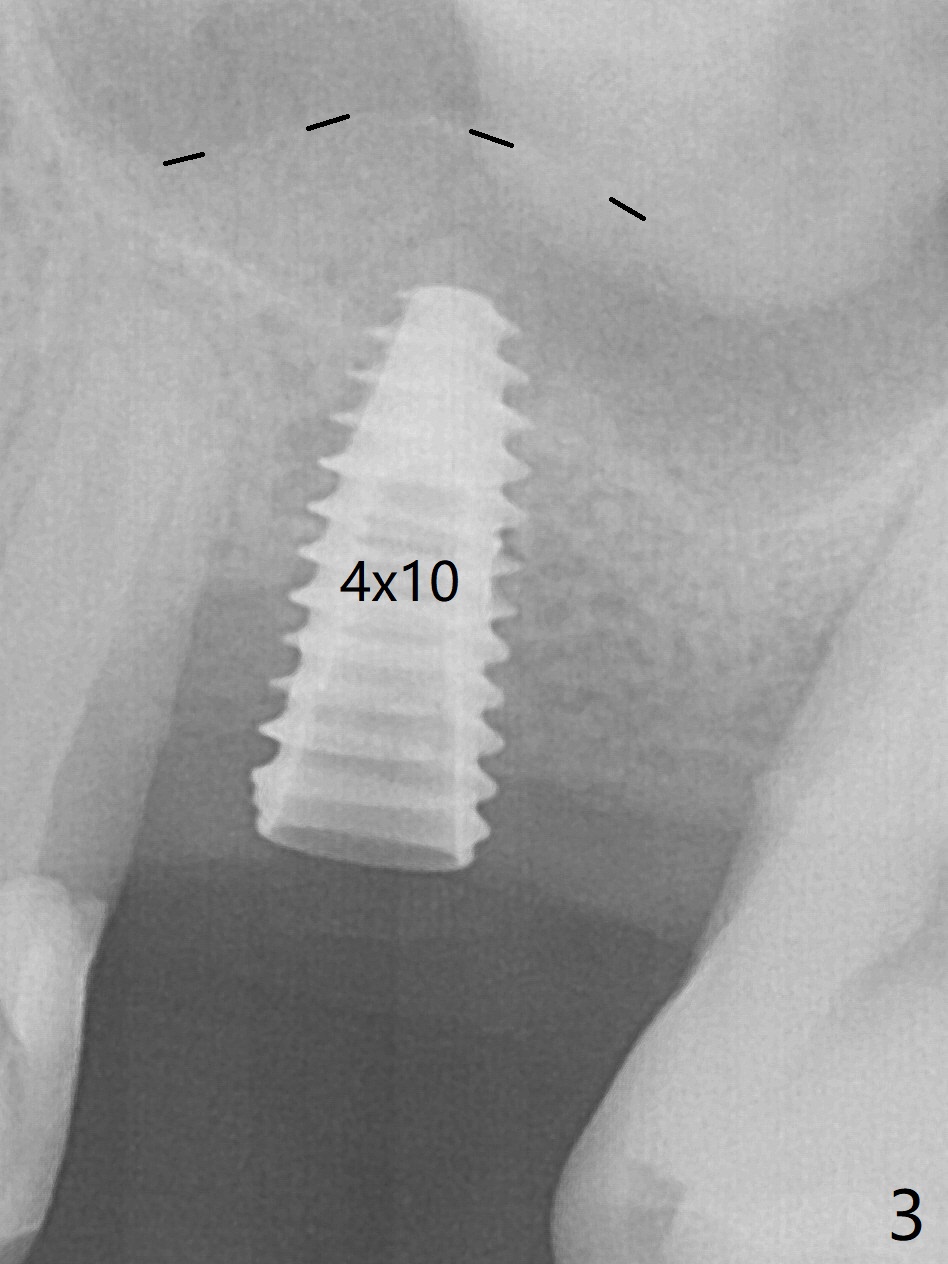

Trajectory of sinus lift without guide at #14 is off (Fig.1 (Magic Sinus Lifter (L) for 9 mm (gingival level)) and needs to be corrected (Fig.2 long line) by re-using 4.8 mm Magic Drill. Following placement of PRF membrane and Demineralized Cortical Allograft (.125-.850 mm) for sinus lift (Fig.3 black dashed line), a 4x10 mm dummy implant is placed with off trajectory. The latter will be fixed by using Lindmann bur to remove the bone distal (Fig.4). The result is less satisfactory with placement of 4.5x10 mm dummy implant (Fig.5). It appears necessary to initiate a new osteotomy (Fig.6 long black line). In fact the result is appealing (Fig.7). The final implant (5x7.3 mm) seems to be placed ideally shown by PA (Fig.8) and BW (Fig.9). Immediately postop CT demonstrates distal defect (Fig.10 *;3-D) and supracrestal placement palatal (Fig.11 P; coronal section). More allograft is then placed in these 2 areas. In all, it is difficult to establish a correct osteotomy without guide. The patient return for uncover 3.5 months postop, although there is a small hole in the middle of the incision (Fig.12). The crown/abutment becomes loose less than 1 month post cementation when the patient chews something tough. It is more related to the unfavorable implant/crown ratio. It is loose again 2 months later. Screw driver is buried inside the abutment with plumber tape. When it is loose for the 3rd time 13 months post cementation, the existing screw driver with a created slot (for retention) is buried without plumber tape after retorque at 35 Ncm (Fig.13). A tissue-level implant should have been used.